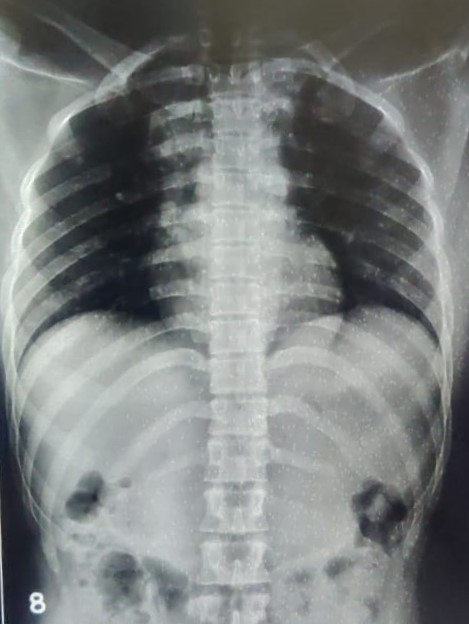

| 4422 | IGGMC, Nagpur, Nagpur | P2 | 29-50 | Vinod Mukardam | Consent taken on Paper | 35 Yrs. |

Provisional Diag : BREATHLESSNESS UNDER EVALUATION

Final Diag : Post TB sequalae (CxR- Bilateral Upper Zone Collapse With Pleural Effusion) |

Post TB Sequelae | Blunting of both lung costophrenic (CP) angles and a trachea shifted towards the right on a chest X-ray | Abnormality visible on x-ray |